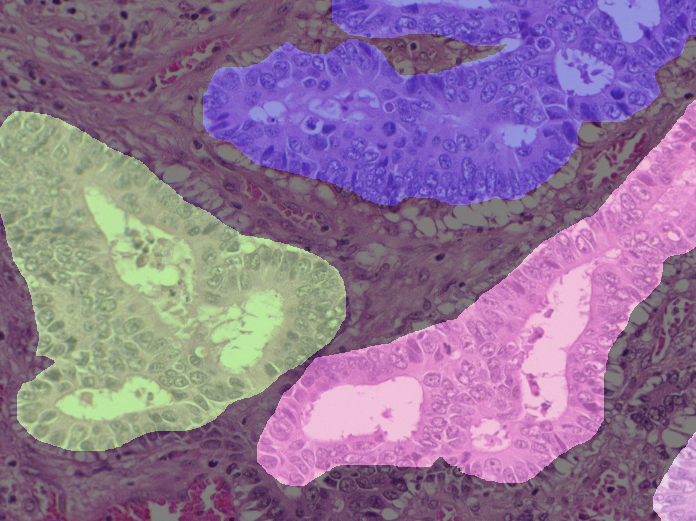

(c) GlaS Image

(f) GlaS True Mask

Figure 6: Panels (a) to (c) depict the input image for each dataset. Panels (d) to (f) represent the true mask for each dataset.

GlaS: Annotated gland segmentation images of Hematoxylin and Eosin stained slides [37].The dataset includes 165165165 manually annotated images of dimensions 522×775×35227753522\times 775\times 3, along with corresponding ground truth masks.

The Figures 6 present examples of input images along with their corresponding true masks for each dataset. The training set comprises 80%percent8080\% of the images, while the remaining 20%percent2020\% is allocated for validation. We trained our model on the training set and evaluated the estimated certainty on the validation set.